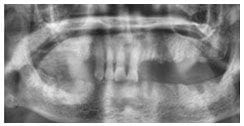

術後X光片